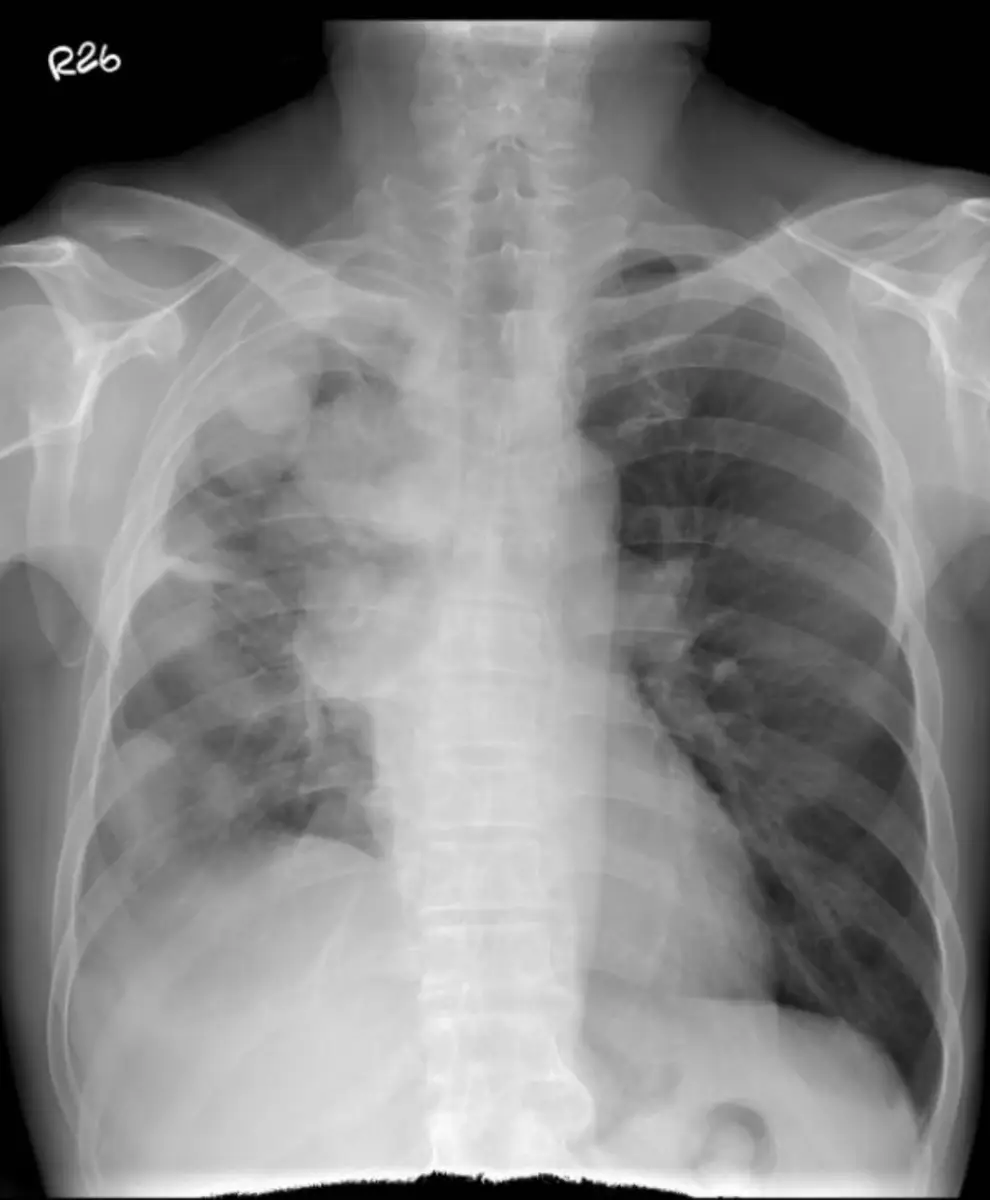

本題 CXR 顯示:右側大量胸腔積液(massive pleural effusion),右肺野幾乎完全呈均勻白化(opacification),肺紋理不清。縱膈腔(心臟陰影)輕度向左偏移,左側肺野充氣良好,無明顯實質性浸潤。無肺門腫大或明顯肺實質腫塊,肋骨無明顯溶骨性破壞。整體影像特徵以大量單側胸腔積液為主,合併右肺葉受壓萎陷,無典型肺腺癌的周邊腫塊、毛刺或空洞表現。此種影像,結合病患有超過十年拆船廠(石棉暴露)工作史,高度提示惡性胸膜間皮瘤而非原發性肺腺癌。

(A) 最有可能的診斷是肺腺癌。 ❌ 這是錯誤敘述,即本題答案。 病患有超過十年拆船廠工作史,石棉暴露史明確。CXR 呈現大量單側胸腔積液,無其他器官轉移。最符合的診斷是惡性胸膜間皮瘤,而非肺腺癌。石棉纖維引起的惡性腫瘤有 20-40 年的潛伏期,與病史完全吻合。肺腺癌通常表